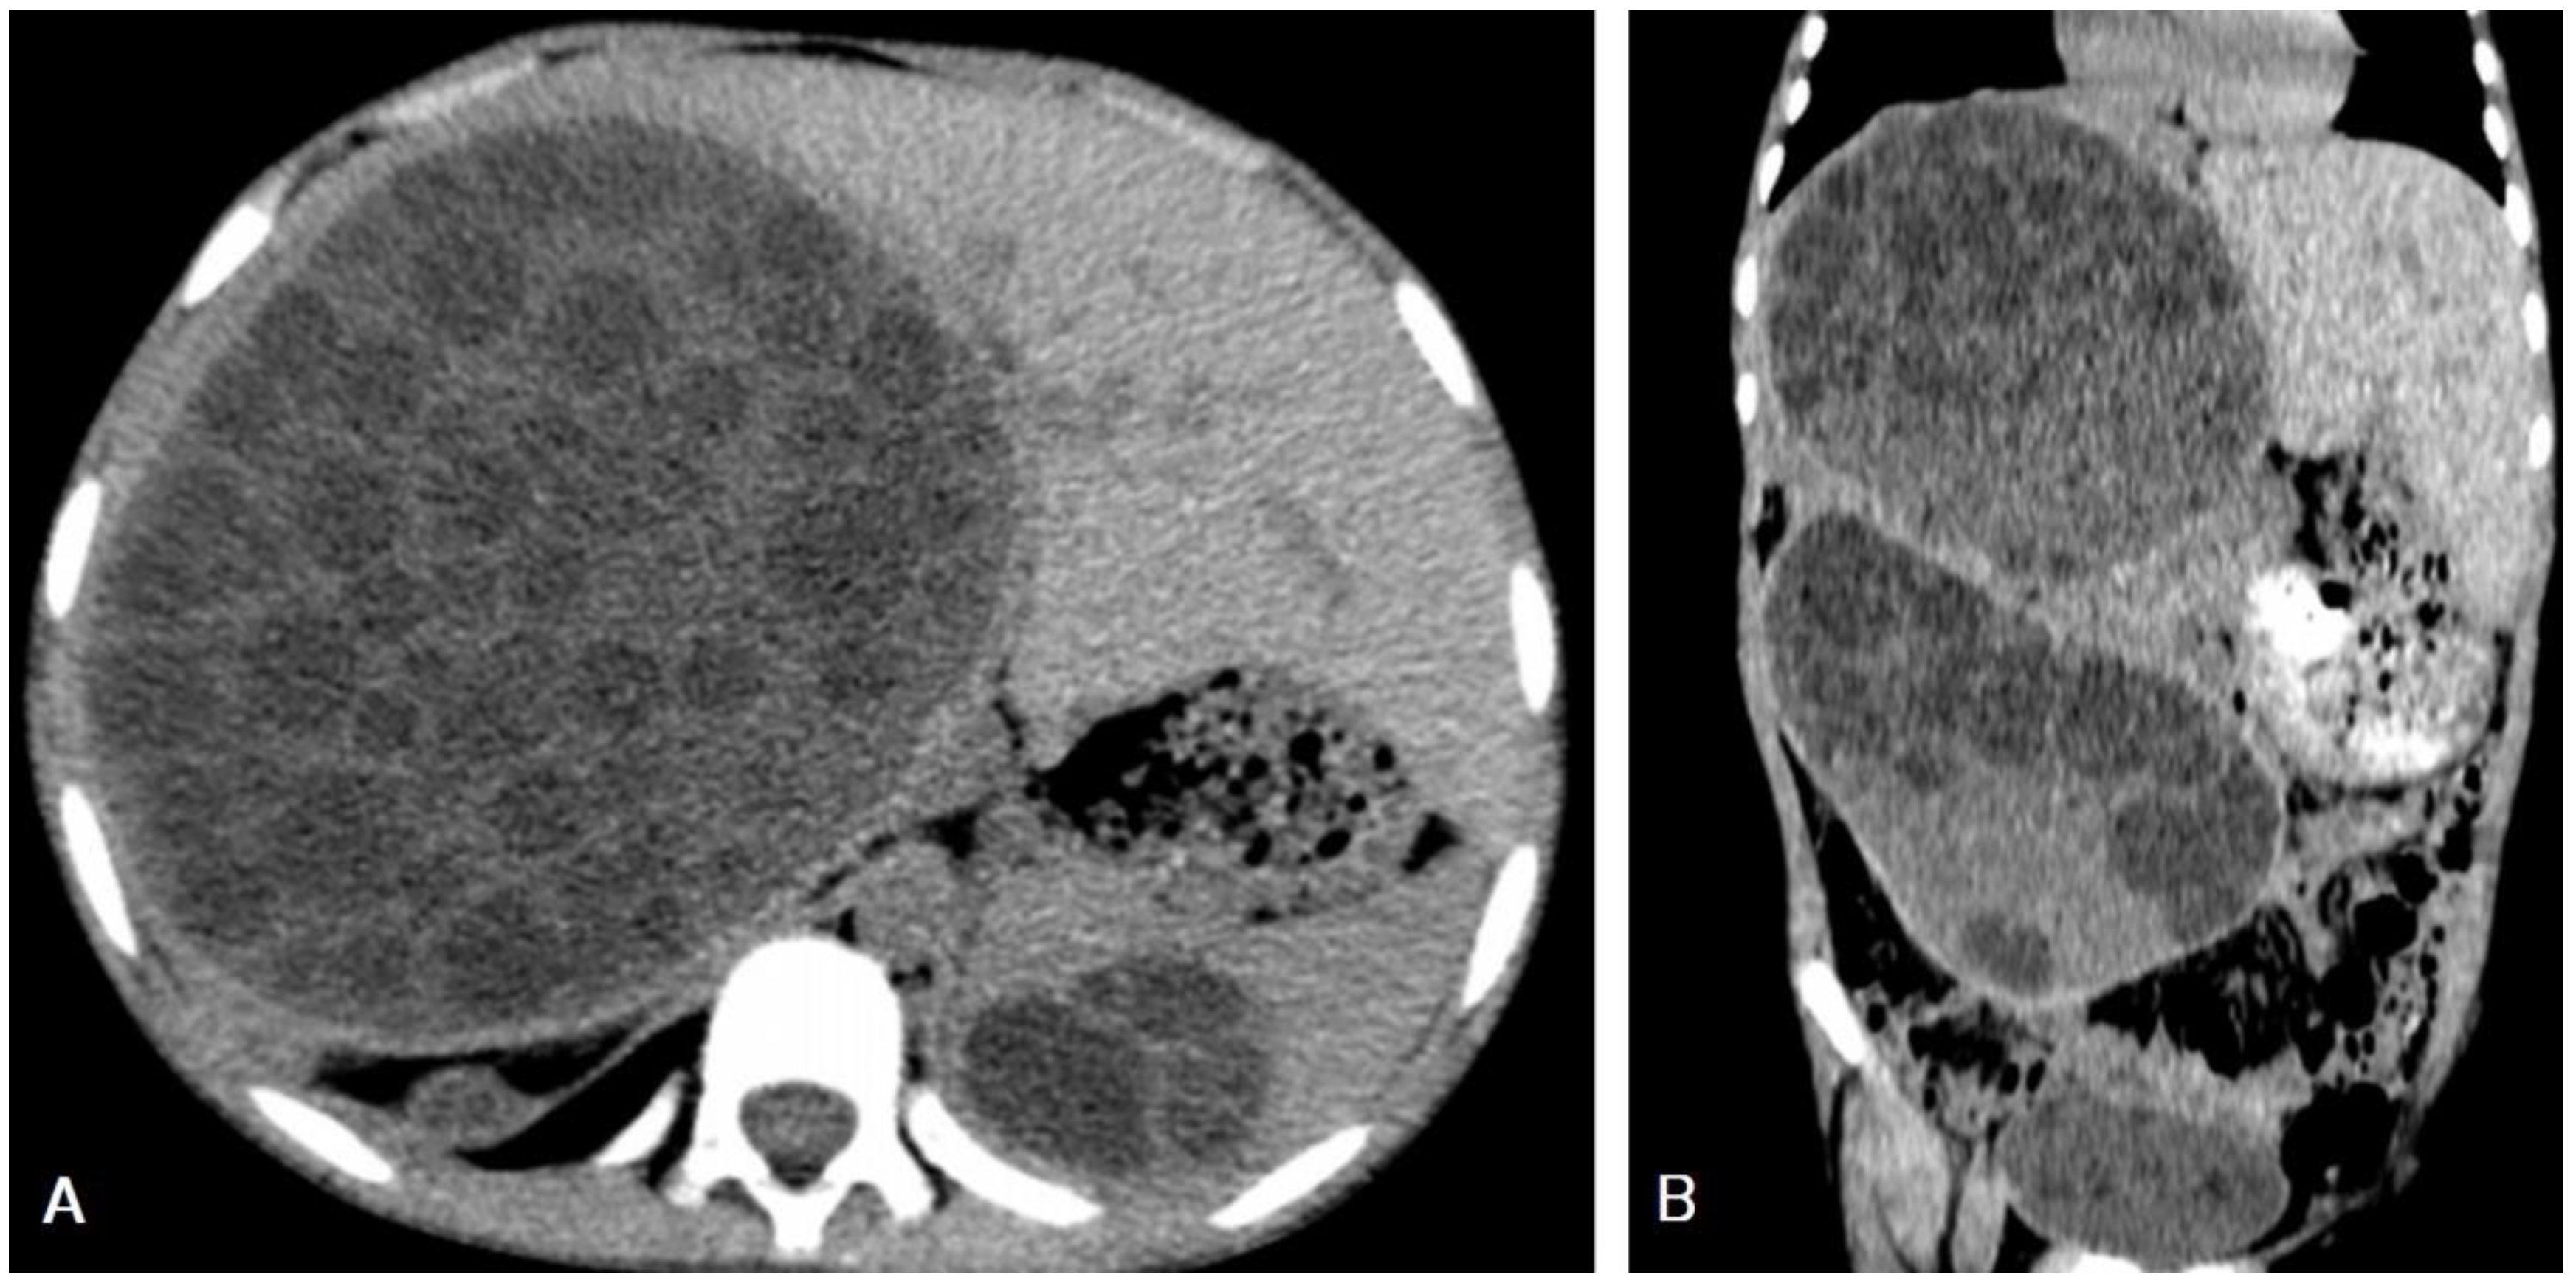

5.1. Hydatid Cysts of the Liver